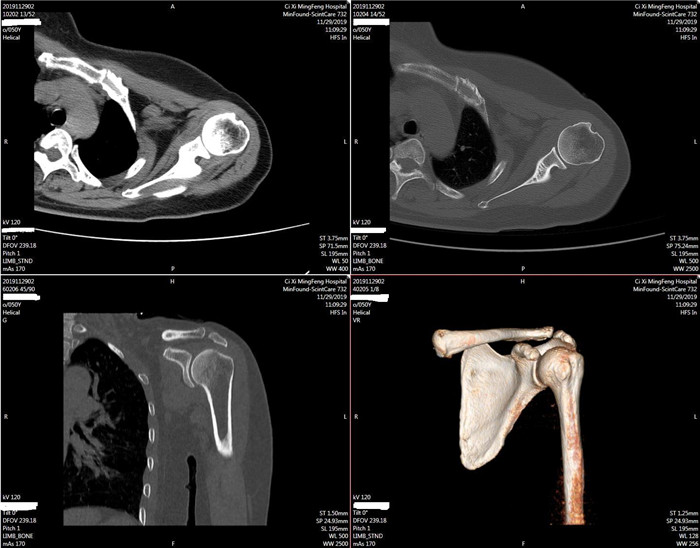

明峰CT搭載了領(lǐng)先的硬件技術(shù)平臺(tái)及系統(tǒng),強(qiáng)大的掃描能力可滿(mǎn)足臨床的各種要求,呈現(xiàn)更極致的細(xì)節(jié),為各臨床科室提供高品質(zhì)的圖像。薄層掃描,消除部分容積效應(yīng),提高各向同性。配合高分辨率算法,有助于細(xì)微結(jié)構(gòu)和形態(tài)學(xué)顯示。